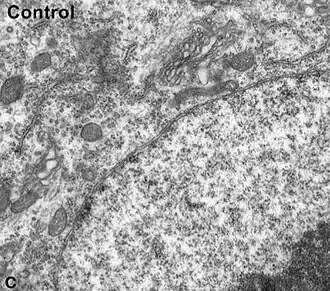

Ultraestructura

Arriba citoplasma con RER y Golgi.

Abajo núcleo (gris claro) y nucléolo (gris oscuro) Microscopía electrónica. Immunogold.

El núcleo es claro, de contorno liso, posee gran cantidad de poros nucleares.[15]

El retículo endoplasmático rugoso (RER) y el aparato de Golgi están bien desarrollados, como es habitual en células con intensa síntesis proteica.

Las mitocondrias son pequeñas pero abundantes, para entregar la elevada energía consumida por el metabolismo.

En el pericarion y en la primera porción de las dendritas se encuentran corpúsculos grandes (cuerpos de Nissl), que faltan en el axón.[14]